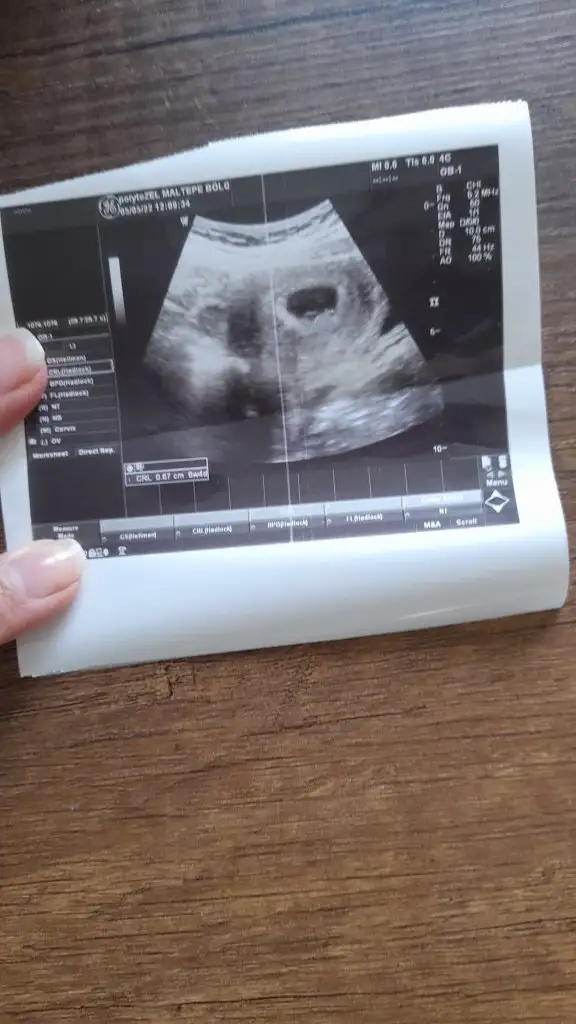

merhaba banada tahminde bulunabilirmisiniz rica etsem.

Karindan ultrasonmerhaba banada tahminde bulunabilirmisiniz rica etsem.